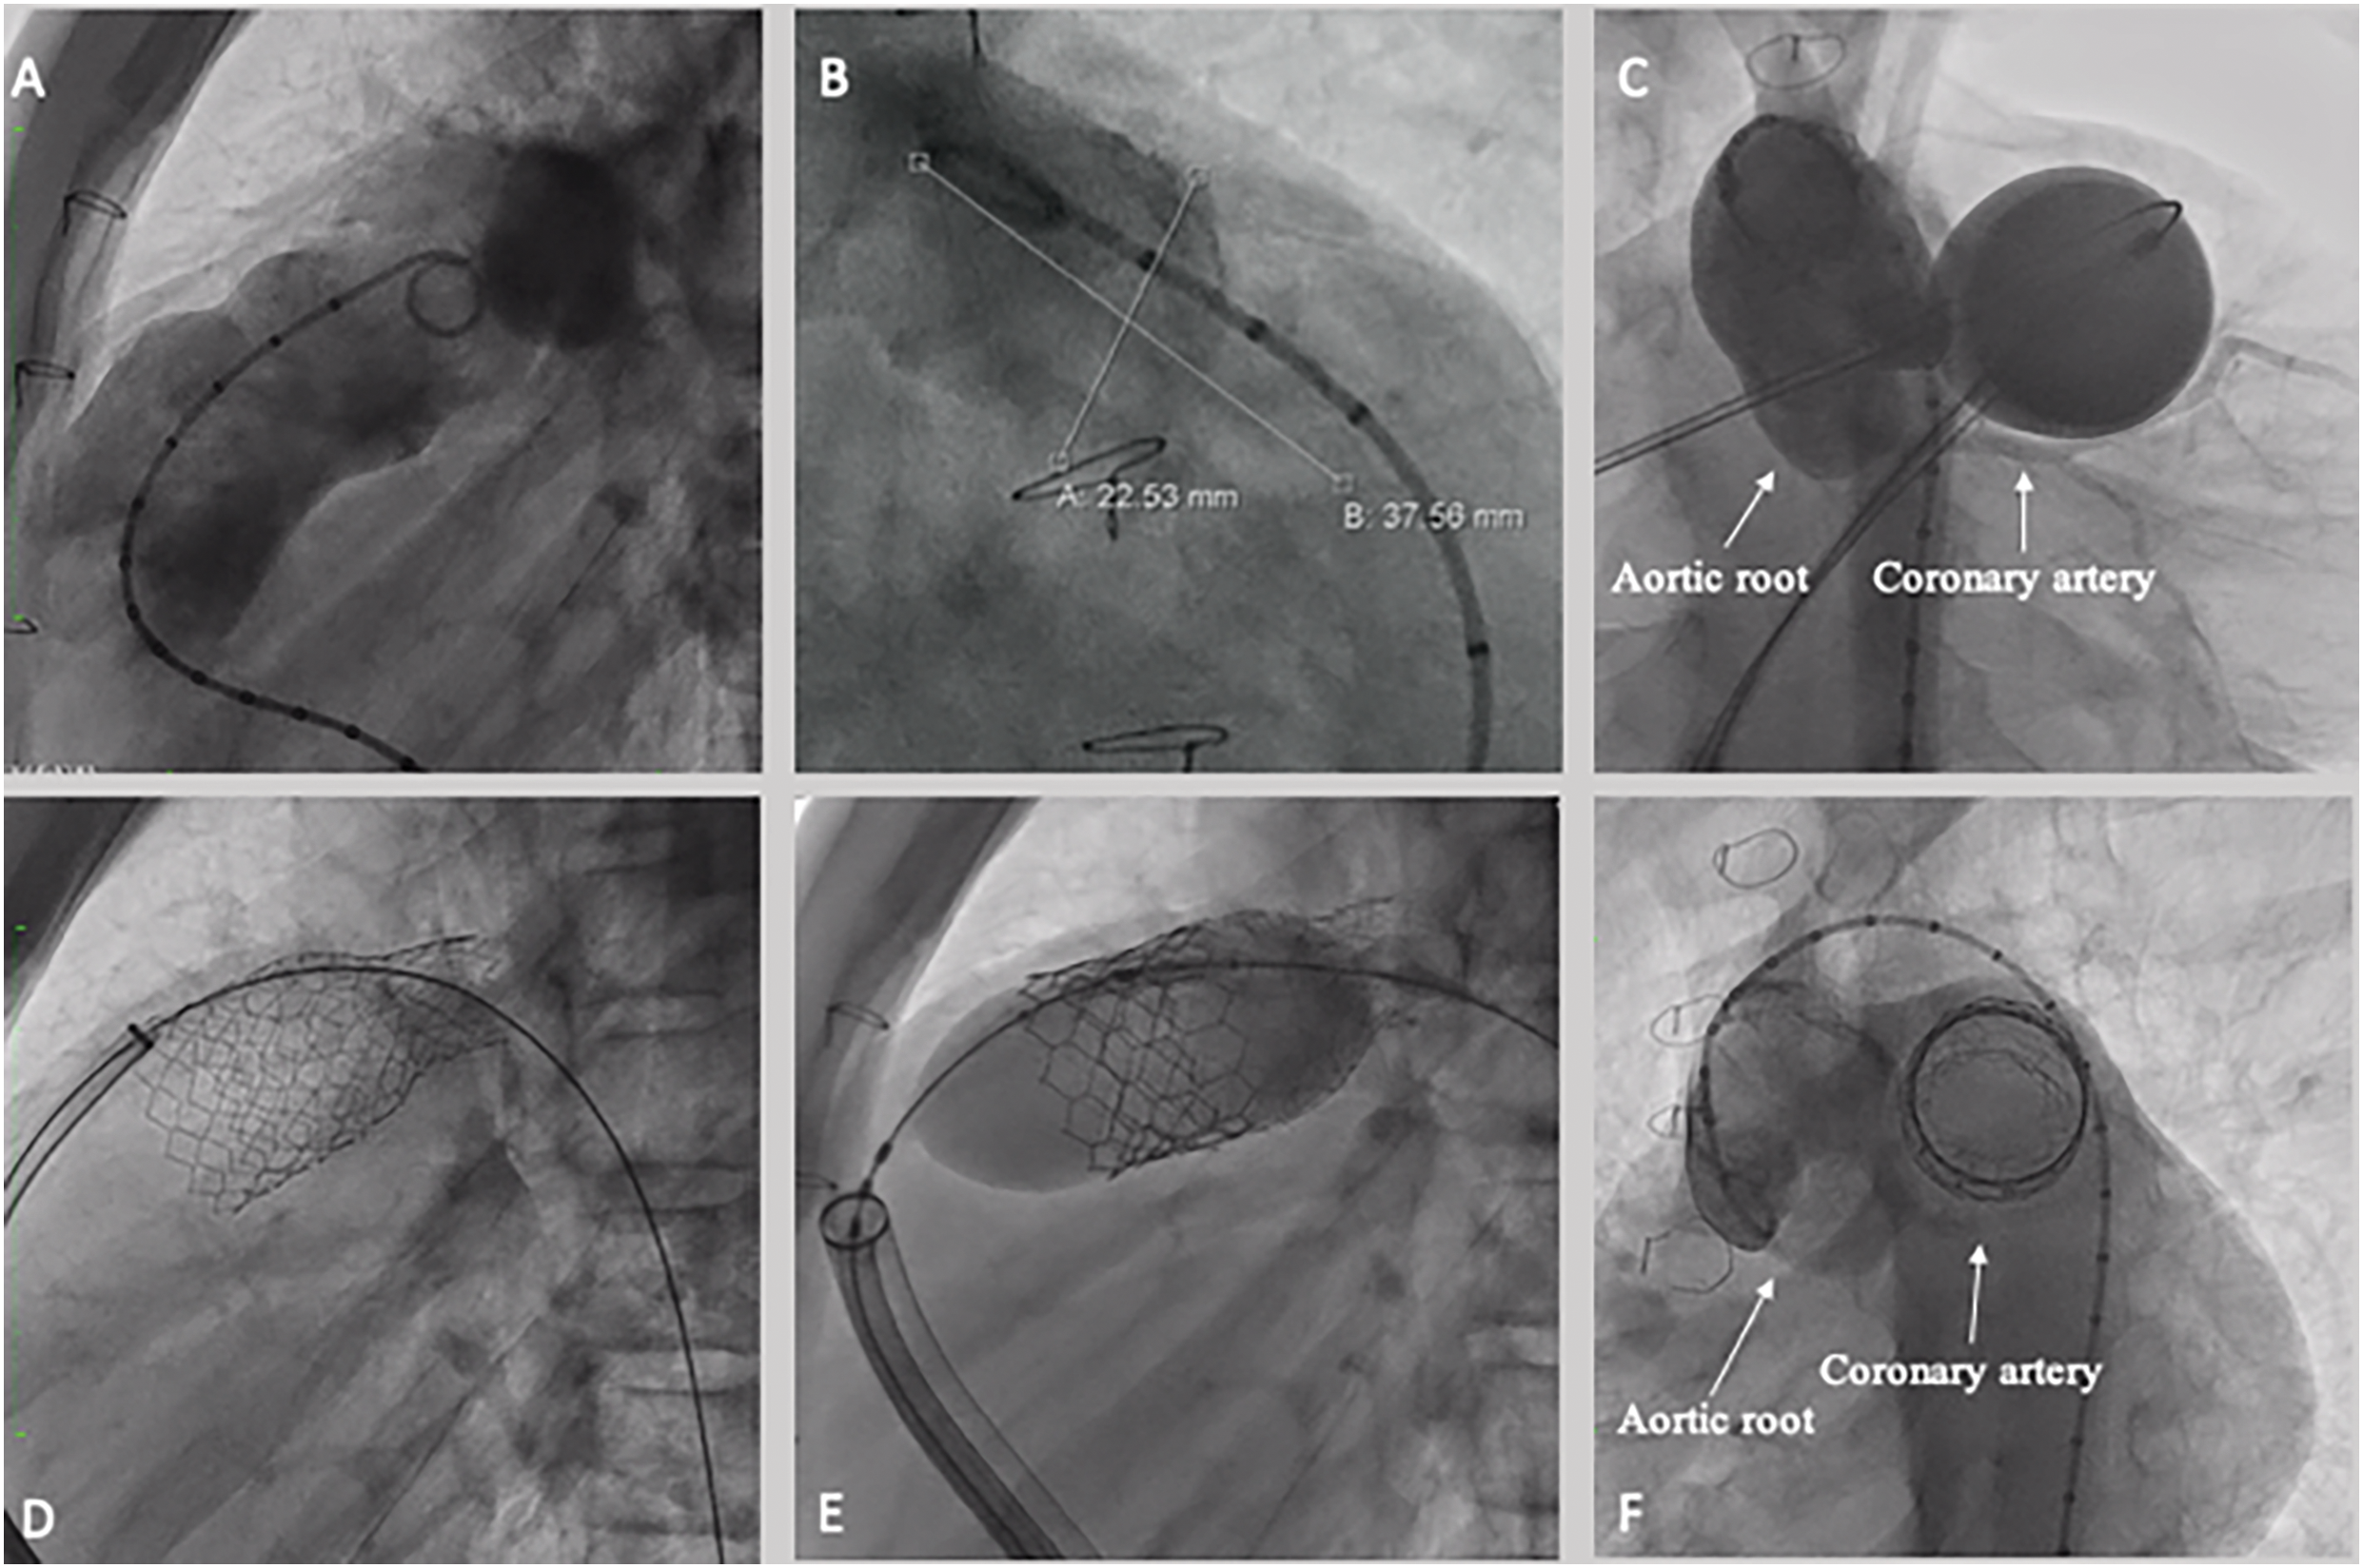

Sapien valves are crimped using a dedicated system and should be used by certified operators. The valve is mounted outside of the balloon, to reduce the whole delivery sheath size. After introduction via the femoral access, the balloon (which features both proximal and distal radio-opaque marker) is advanced through the RVOT and aligned to the stent. The valve is delivered within the sheath up to the deployment site. To enhance the system trackability and to reduce the risk of iatrogenic tricuspid valve injury, the valve is advanced in a 26 Fr Dry-Seal long-sheath (WL Gore, Flagstaff, AZ, USA). Once the valve reaches the RVOT, the sheath is retracted to expose the valve. The ensemble can be angulated using a flex wheel to facilitate the crossing of kinking or acute angles but before deployment, the system should be straightened again and the valve fully uncovered before balloon inflation (Fig. 2).

Figure 2: Sapien S3 valve implantation. (A) RVOT angiography demonstrating landing zone on the distal trunk, 23 mm large (B). (C) Aortic root angiography during balloon interrogation, no significant aortic root distortion or coronary compression were detected. (D) Pre-stenting by using a 57 mm Andra stent XL, was implanted from the left pulmonary artery, intentionally jailing the right pulmonary artery, by using a 18 mm × 60 mm Atlas Gold Balloon. The stent was dilated proximally by using a 26 × 40 atlas gold balloon; Finally, a 29 mm Sapien S3 valve was deployed (E). (F) Final aortic root angiography after valve deployment demonstrated no complication on the aorta and coronary tree